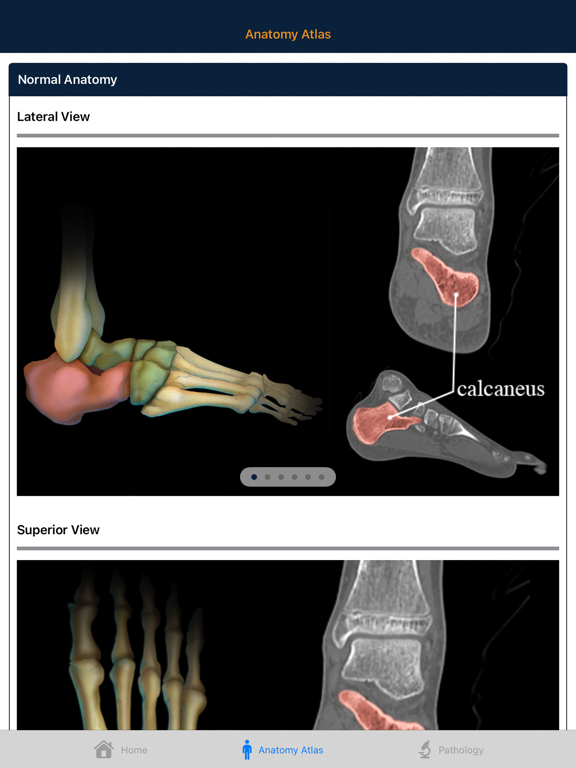

Understanding complex bony Anatomy and Pathology of the Foot and Ankle is essential to the interpretation of musculoskeletal CT. The anatomy of the ankle is complex and in the past CT evaluation of the ankle was often limited to axial slices and simple multiplanar reconstructions. However improvements in CT scanning technology now allow thin collimation and isotropic datasets. These advances along with easy to use 3D software have improved our ability to image the ankle with volume display. It is important for the radiologist to be familiar with the anatomy in all 3 dimensions.

This atlas aims to educate the radiologist with respect to normal and pathological anatomy through case studies and artist rendered interactive 3D models and illustrations. Radiology professionals will have a better understanding of ankle and foot bony anatomy after using this atlas.